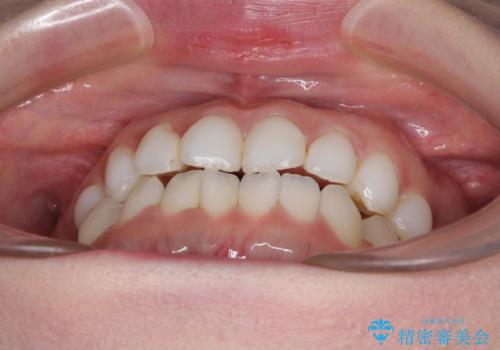

前歯のデコボコをすっきりと インビザライン矯正

- 前歯のデコボコを治したいとのことで来院された患者様です。

下顎が前方位にある方であったため、下顎の歯列全体の後方移動とIPR(歯と歯の間を削る)によってデコボコが解消するように設計し、インビザラインにより治療を行うこととしました。